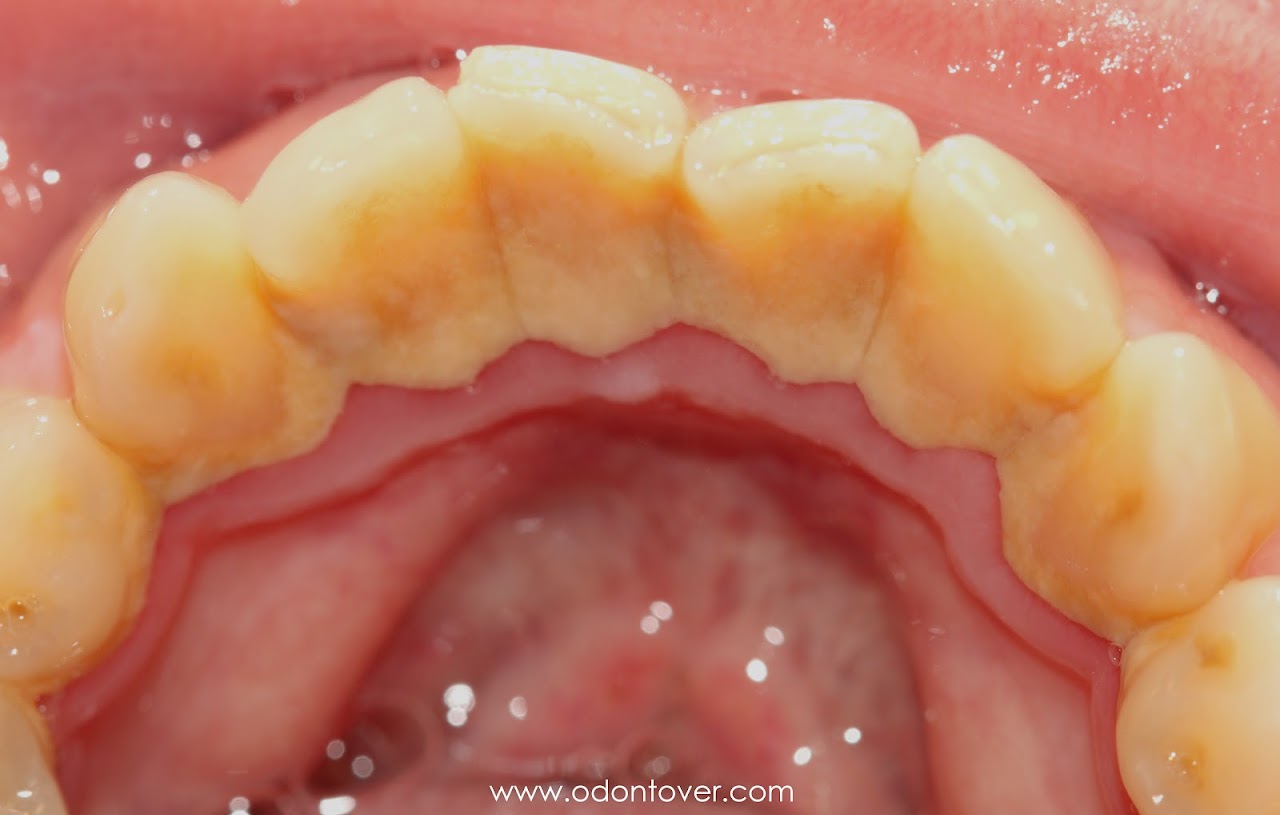

Antes de la profilaxis ultrasónica

Antes: acúmulo de sarro y pigmentaciones, ¿puedes notar la franja de sarro calcificado entre los dientes y la encía?